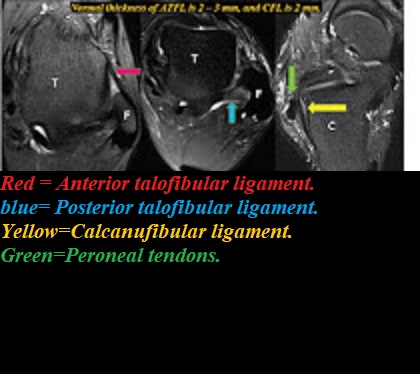

Ankle & Foot MRI Get link Facebook X Pinterest Email Other Apps - February 02, 2020 Reference Get link Facebook X Pinterest Email Other Apps Comments